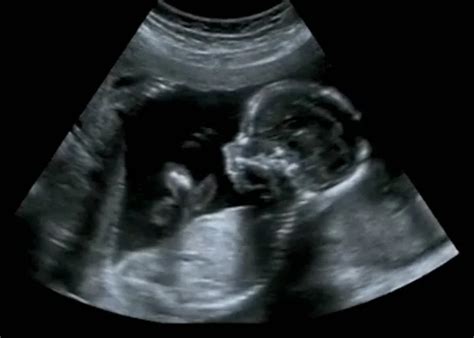

A terhesség átlagosan 40 hétig tart, melyet három részre (trimeszterekre) osztunk. Az első 12 hetet az első trimeszternek nevezzük. Ebben az időszakban általánosságban jellemző a hangulatingadozás, a szorongás, a bizonytalanság érzése, a fáradékonyság és a fokozott alvásigény is. A megtermékenyülés utáni első 14 nap a sejtosztódásról és az embrió anyaméhbe történő beágyazódásáról szól. A 15. naptól kezdődik az embrió fejlődése. A szervek és szervrendszerek kialakulása a 12. hétig tart. Az ultrahangvizsgálat során a 4-5. héttől látható a petezsák, ekkor már megállapítható a terhesség, azonban az élő terhesség csak a szívműködés megjelenésével, a 6-7. héten mondható ki.

A tizedik héten az embrió kezd egyre emberibb formát ölteni, ráadásul egy nagyon kockázatos fejlődési szakasz végét is eléri. Eddig ugyanis rendkívül nagy a kockázata a fejlődési rendellenességek kialakulásának, ami akár a helytelen táplálkozás, a stresszes életmód vagy egyéb környezeti hatások miatt is bekövetkezhet. Az ultrahangon már jól látható a magzat. A feje ebben a fejlődési szakaszban a testéhez képest nagy. A fejét emelgeti és nyújtózkodik. Egyre gyakrabban mozog, egyelőre koordinálatlanul. A karok végén már kialakult a csukló és kifejlődnek az ujjak az ízületekkel együtt. Az ujjak és a lábujjak közti hártya ennek a hétnek a végére teljesen eltűnik, valamint a hüvelykujjak és a mutatóujjak elválnak egymástól. A magzat hamarosan képes lesz mozgatni az ujjait és ökölbe szorítani a kezét. Ez az első olyan mozgás, amely koordinációra utal. Az ujjak kialakulása a méhen kívüli életre való felkészülés első lépése. Hamarosan kialakul a szopóreflex, amely később az újszülött táplálkozásához fontos lesz. Ezt a magzat úgy gyakorolja, hogy a hüvelykujját a szájába veszi. A védőnő a doppler ultrahangvizsgálat segítségével ellenőrzi a szívverését. Ikerterhesség esetén a védőnő két szívverést fog hallani.

A szülész-nőgyógyász ultrahanggal megvizsgálja a várandós nő belső nemi szerveit és a méh üregében lévő embriót, illetve megállapítja a terhességi kort, mely esetenként eltérhet az utolsó menstruáció alapján számítottól. Ez esetben a korrigált terhességi kort veszik irányadónak. Az első vizsgálat után általában 4 hetente kerül sor ismételt vizsgálatra. Ezen alkalmak mindegyikén vérnyomás-, pulzus- és testsúlymérés, vizeletellenőrzés, a méhszáj állapotának vizsgálata és a terhesség fejlődésének követése történik. Ezeken kívül az orvos szükség szerint különböző vizsgálatokra irányíthatja, beutalhatja a kismamát.

Az első trimeszterben elvégzendő vizsgálatok: laboratóriumi vizsgálatok: teljes vérkép, vércukorvizsgálat, vércsoport-meghatározás, szifiliszszerológiai szűrés, anyai hepatitis B-hordozás szűrése, vizeletvizsgálat (és egyéb, az orvos által elrendelt vizsgálatok); szülészeti-nőgyógyászati vizsgálatok: citológiai vizsgálat (sejtek vizsgálata), hüvelyváladék-tenyésztés, emlő vizsgálata, általános nőgyógyászati vizsgálat; 12-13. héten az első ultrahang-szűrővizsgálat; általános belgyógyászati vizsgálat; fogászati vizsgálat.

A 12.-14. hét között kerül sor a magzat első genetikai szűréseire, a 12. heti UH vizsgálatra és kombinált szűrésre, melyből az első trimeszteri genetikai ultrahangvizsgálat kötelező. A kombinált teszt Fetal Medicine Foundation (FMF) rendszerű kiterjesztett genetikai szűrővizsgálat, melyet a terhesség 11-13. hetében végzünk, ultrahangvizsgálat és vérvizsgálat kombinációjával.